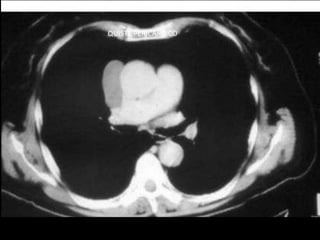

• Radiografía de tórax

• Tomografía axial computada

TOMOGRAFIA